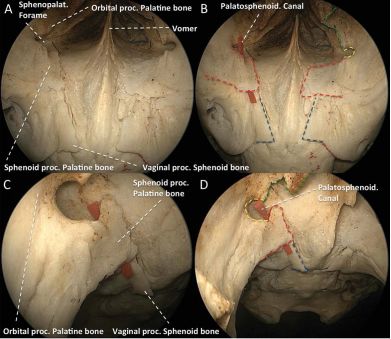

内镜下显露左侧蝶腭孔和蝶腭动脉(SPA)。a、切口位于中鼻甲(MT)根部前方、上颌窦窦口后囟(PF)后方。NS 鼻中隔,PC 后鼻孔。b、暴露腭骨垂直板(VPP)和其构成蝶腭孔前界的眶突(OP)后,从腭骨筛嵴(EC)上剥离中鼻甲基板(BL)。EC位于SPA前内侧,是定位后者的重要标志。c、显露SPA往鼻中隔和鼻腔外侧壁的分支(分别为s和n)。

内镜下暴露左侧的腭鞘管(或者称为咽管,PC):腭骨眶突及临近的上颌窦后壁骨质已经去除,因此蝶腭孔得以显露并且可以往外侧牵拉蝶腭动脉(SPA)。C 斜坡,FLS 蝶窦底壁,SF 鞍底,pcICA 斜坡旁段颈内动脉。a、该例标本腭骨垂直板(VPP)上的蝶突(SP)菲薄,可被剥离子轻易骨折,其构成PC的下内侧壁。b、该标本SP厚硬,必须由磨钻去除。

内镜下显示左侧的咽动脉(PA):C 斜坡,pcICA 斜坡旁段颈内动脉,PPF 翼腭窝,SF 鞍底。a、去除腭骨垂直板(VPP)上的蝶突后可显示后上方走形于蝶窦底的咽动脉(PA)。b、切断PA并外移PPF内容物可暴露恰好位于腭鞘管外侧的翼管(VC)。c、咽沟(pharyngeal groove,PG)位于蝶骨底的鞘突,去除腭鞘管的内容物后可见。

内镜下观察翼腭窝后壁及相关区域。a、翼腭窝后壁可以辨认出三个开口,从内向外依次为:1)咽管(PC),从翼腭窝后内侧走向蝶窦底;2)翼管(VC),在蝶窦底往后走形并指向颈内动脉;3)圆孔(FR),其内走形有上颌神经(V2),并且可见v2的海绵窦段(V2s)和翼腭窝段(V2p)。FR上方为眶上裂(SOF)的后内部分。ICA 颈内动脉,OT 视神经,PPG 翼腭神经节,pwMS 上颌窦后壁,SP 腭骨蝶突,SPA 蝶腭动脉。b、通过往下外方向牵拉SPA和PPG可以暴露构成翼腭窝后壁的翼突根部(BPP)。IMA 上颌动脉。